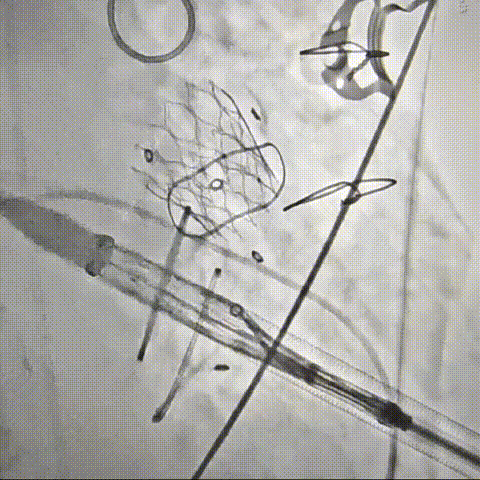

DSA下钢针穿刺心尖,建立心尖入路

输送系统沿加硬导丝进入

瓣膜初次释放,位置稍浅

目标深度:瓣环平mark点

部分回收后,调整瓣膜深度重新释放,瓣膜位置良好

无张力脱钩,瓣膜位置稳定

闭合输送系统后撤除体位,

收紧心尖荷包